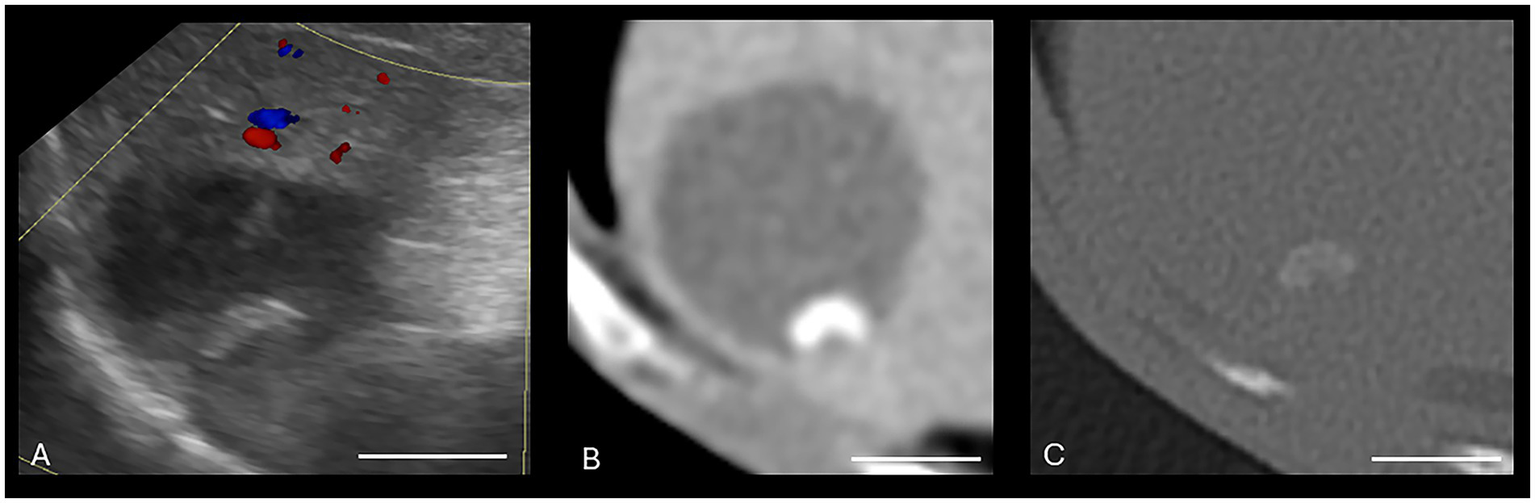

Both US and CT successfully identified the one gallbladder wall mass (malignant carcinoid) (Figure 1). Ultrasound and CT performed equally well in identifying all six gallbladder mucoceles, with no discordant pairs and an ICC of 1.0 (Figure 2). The imaging characteristics of all gallbladder mucoceles were consistent with those previously described (8–10).

Figure 1. Canine malignant gallbladder carcinoid on CT and US. (A) Longitudinal B-mode ultrasound image of the gallbladder. There is an irregularly marginated, hyperechoic mass present within the gallbladder. (B) Same mass with color Doppler interrogation. The mass displayed a high vascularity on color Doppler interrogation. (C) Dorsal plane, soft tissue window, arterial phase post-contrast image (WW = 400, WL = 50) of the same patient. (D) Transverse plane, soft tissue window, post-contrast arterial phase (WW = 400, WL = 50) of the same gallbladder wall mass. The white calibration bar at the bottom right of each panel delineates 1.0 cm.